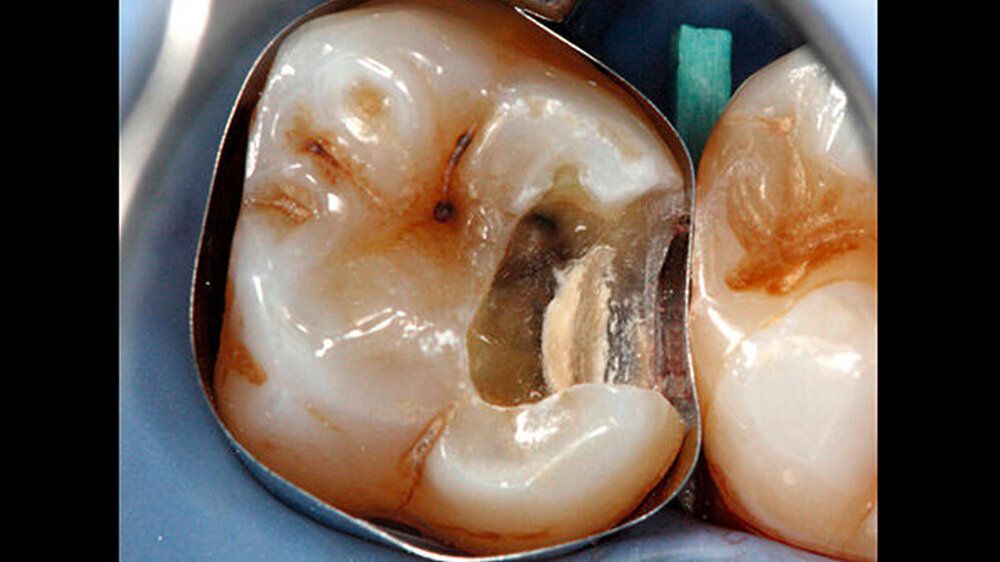

-Schnee war positiv. Die Behandlung wurde auf Wunsch des Patienten ohne Lokalanästhesie durchgeführt. Vor der Präparation erfolgte das Anlegen von Kofferdam an den Zähnen 24 bis 27. Zunächst wurde mit rotierenden Diamantschleifern unter Wasserkühlung von okklusal ein Zugang zum Defekt geschaffen. Der distale Kavitätenbereich wurde mit oszillierenden Instrumenten präpariert (SonicFlex, KaVo) (Abbildung 2). Dabei wurde die Kavität so zierlich wie möglich gestaltet.

Anschließend erfolgte die Kariesexkavation mit Rosenbohrern unter optischer Kontrolle mit einem OP-Mikroskop. Die Kavität wurde im Verlauf der Exkavation mehrmals mittels FACE (fluoreszenzgestützter Kariesexkavation, SIROinspect, Sirona) auf Residualkaries überprüft [Buchalla W et al., 2013].

Bei der vollständigen Kariesentfernung kam es nicht zu einer Freilegung der Pulpa (Abbildung 3). Anschließend wurde eine Metallmatrize (HaweTofflemire Matrize, Kerr Dental) angelegt und verkeilt. Die Kavität wurde gereinigt und getrocknet.